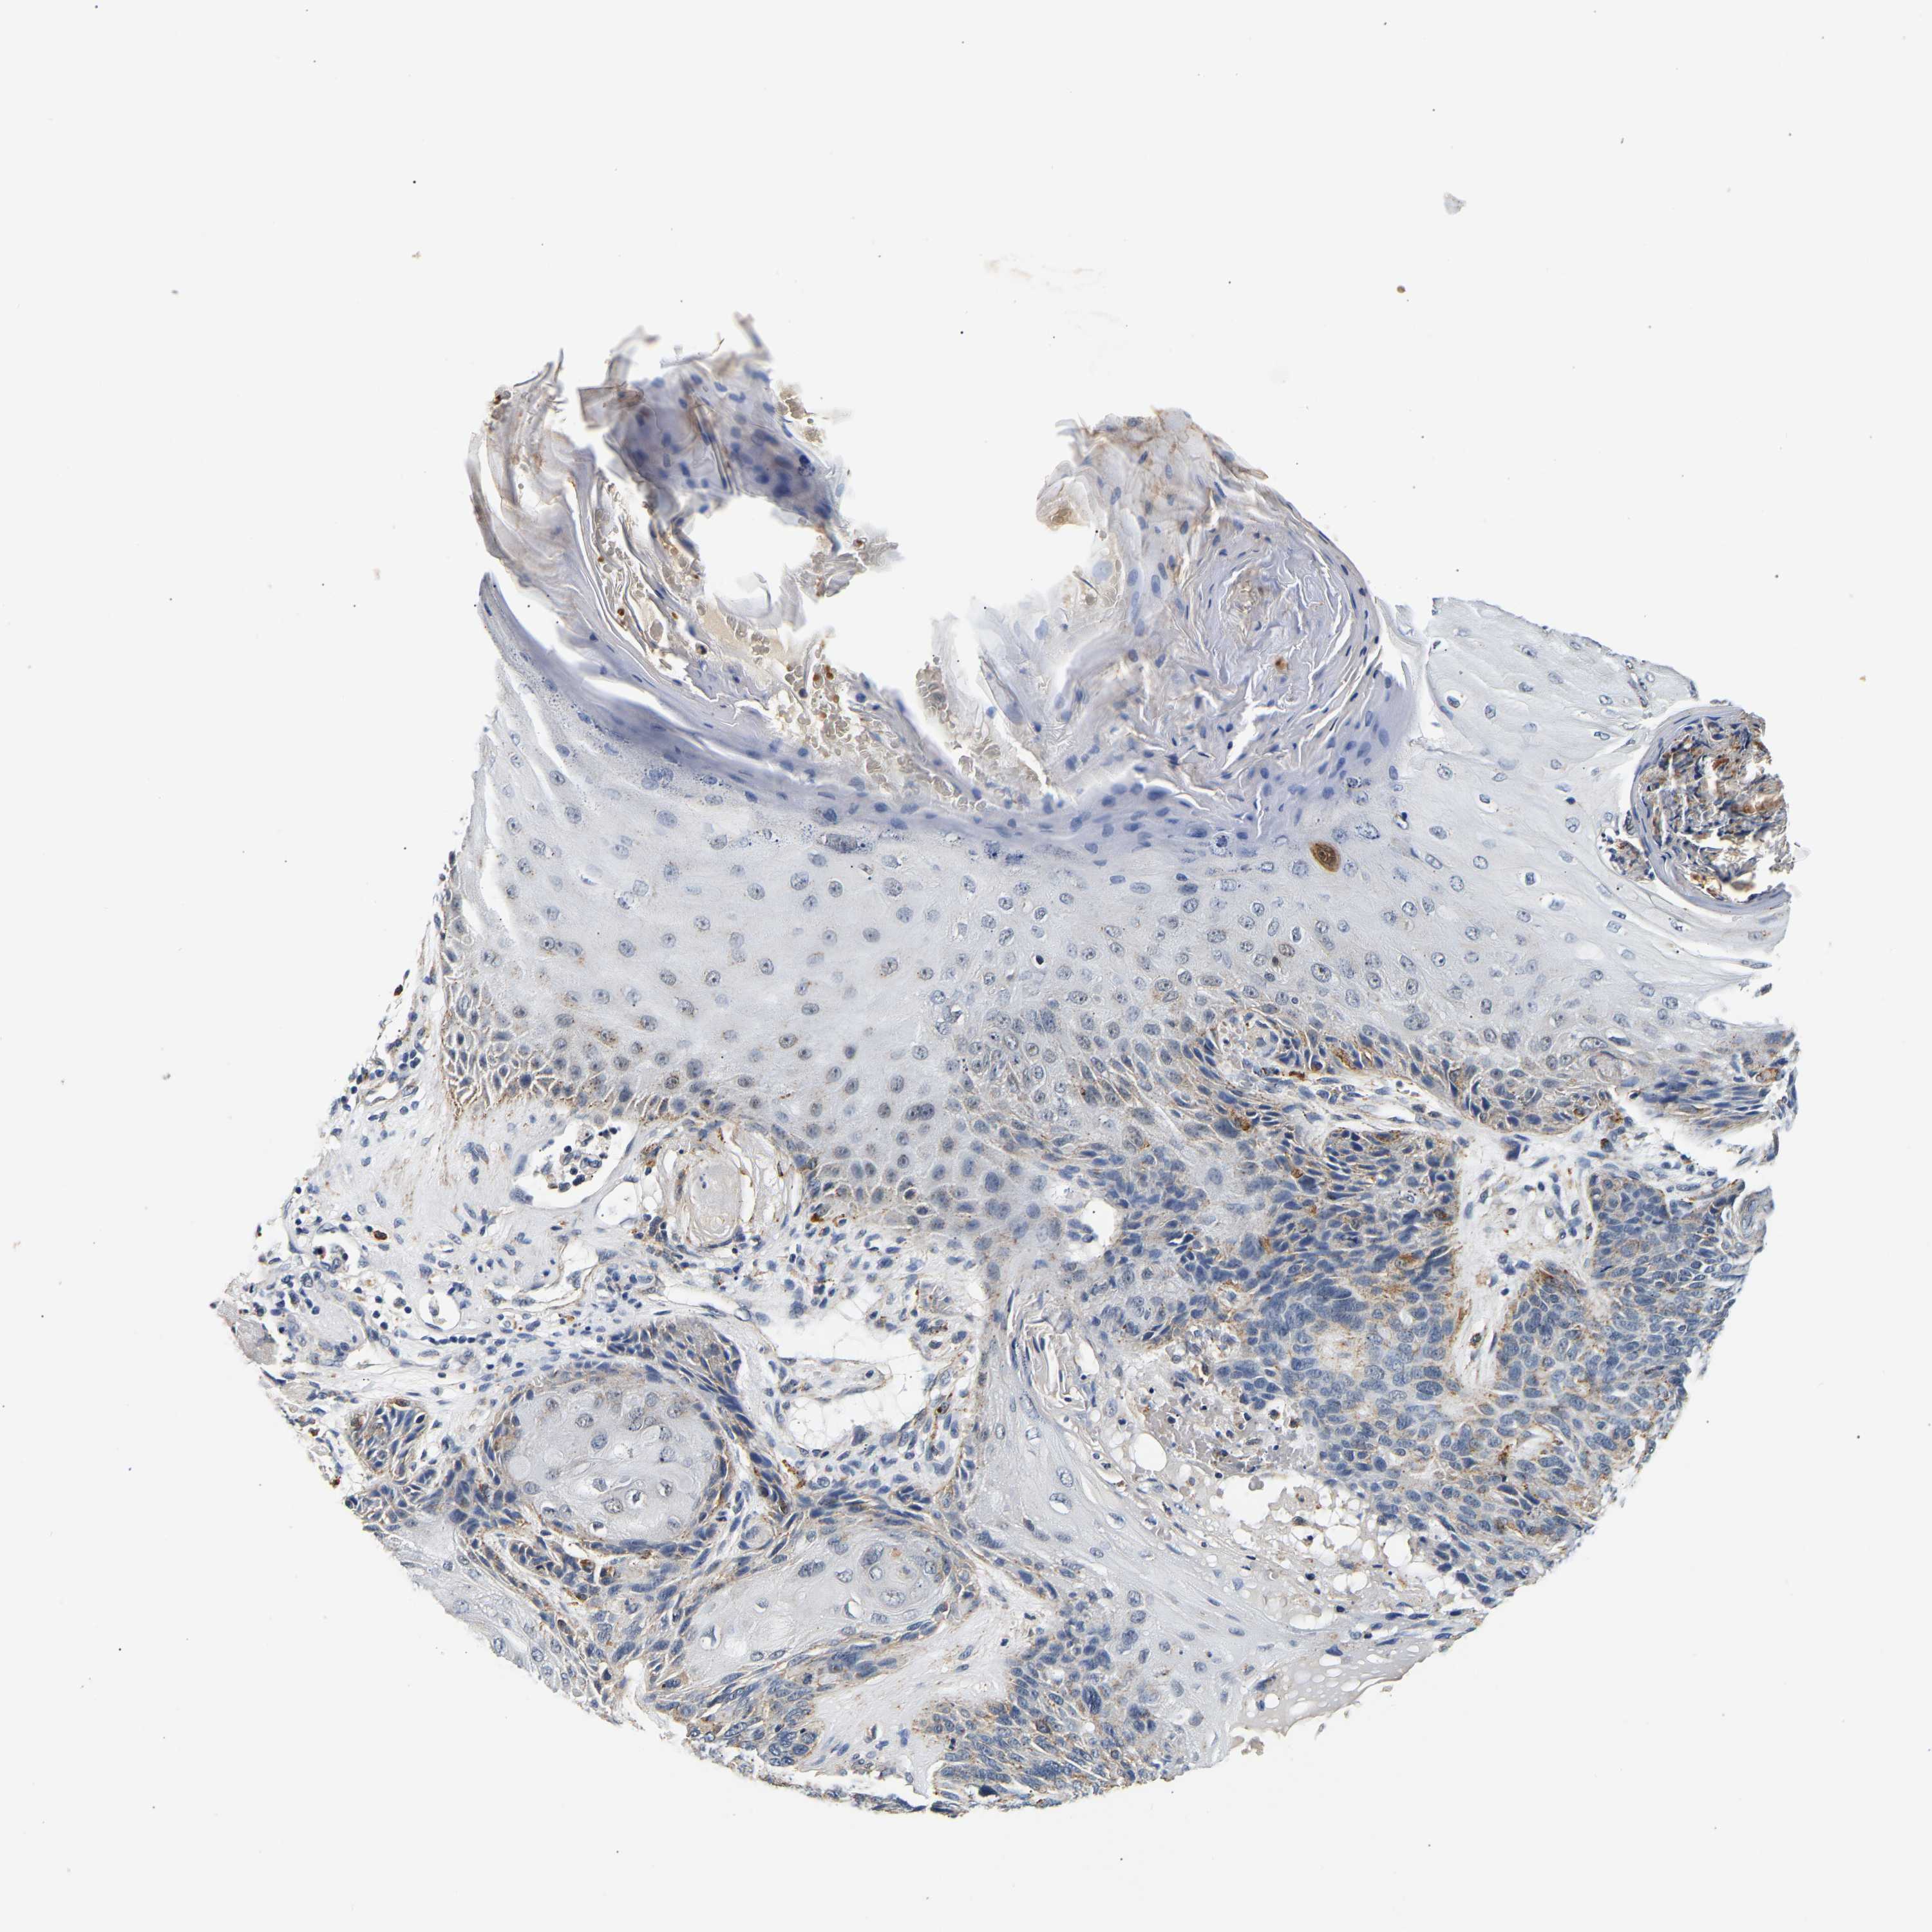

Basal cell and squamous cell cancer

SKIN CANCER - Protein expressioni

A mouse-over function shows sample information and annotation data. Click on an image to view it in a full screen mode. Samples can be filtered based on level of antibody staining by selecting one or several of the following categories: high, medium, low and not detected. The assay and annotation is described here.

Antibody stainingi

Antibody staining in the annotated cell types in the current human tissue is reported as not detected, low, medium, or high, based on conventional immunohistochemistry profiling in selected tissues. This score is based on the combination of the staining intensity and fraction of stained cells.

Each image is clickable and will lead to virtual microscopy that enables deeper exploration of all samples and also displays staining intensity scores, fraction scores and subcellular localization as well as patient and tissue information for each sample.

Antibody HPA019708

Staining

High

Medium

Low

Not detected

Intensity

Strong

Moderate

Weak

Negative

Quantity

>75%

75%-25%

<25%

None

Location

Nuclear

Cytoplasmic/membranous

Cytoplasmic/membranous,nuclear

Squamous cell carcinoma, metastatic, NOS